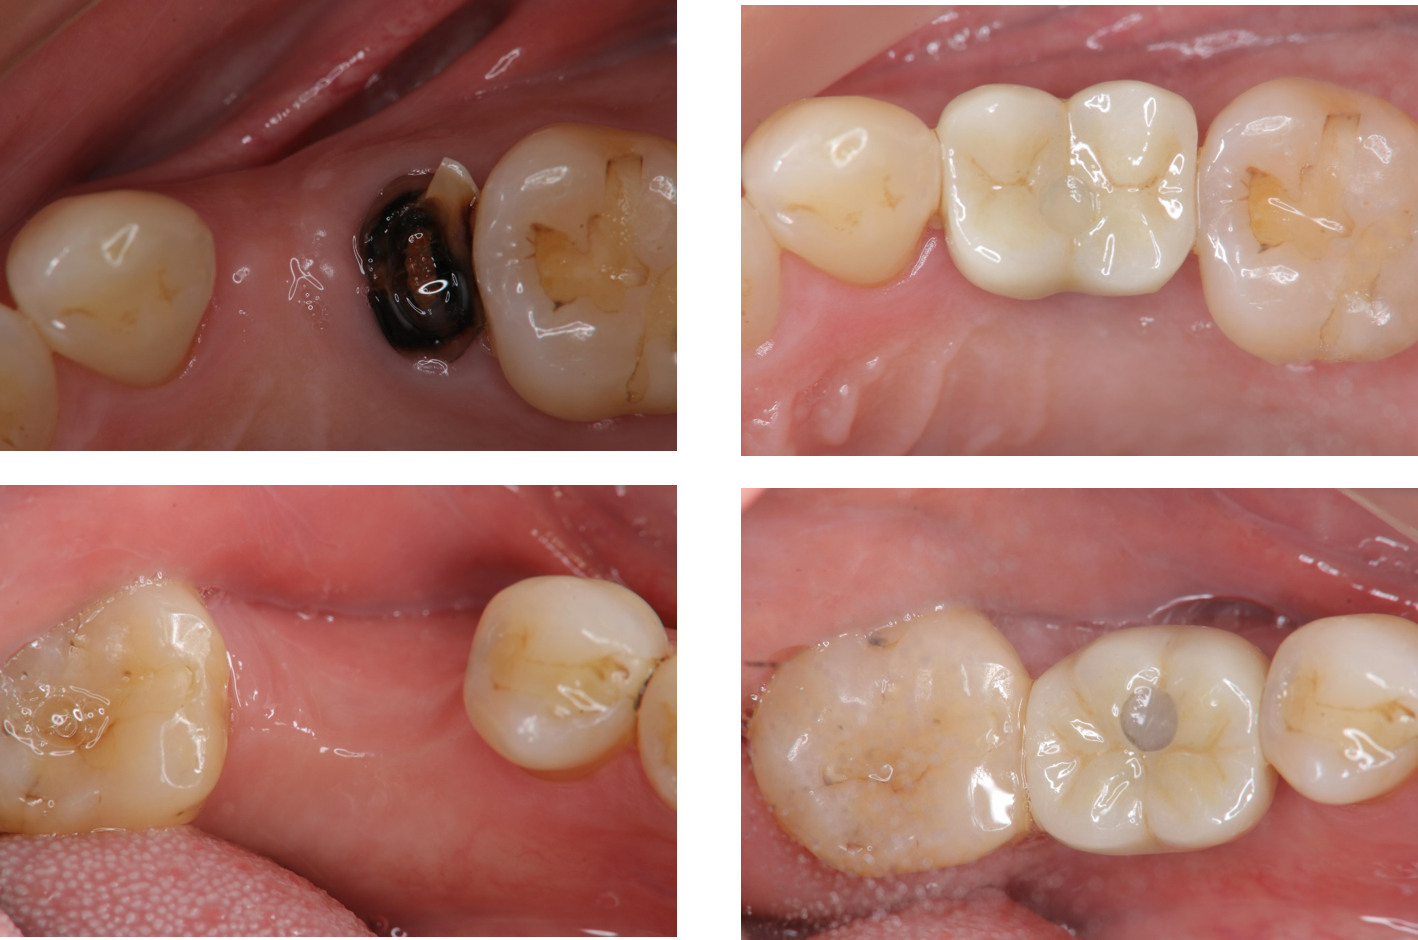

治療前,左下第一大臼齒嚴重蛀牙

治療前,蛀牙至牙根處

治療後,上顎植牙口內適應良好

治療後,下顎植牙口內適應良好

術前、術後比較